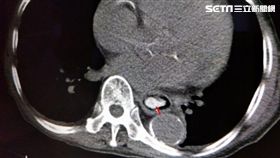

魚卵卡食道喝水更嚴重 醫曝緊急解方

高雄有一名90歲的老翁,他在品嘗魚卵的時候吞嚥太急,...

狂流口水想吐 竟是食道卡一顆榴槤籽

台中一名高齡92歲的曾姓老翁,年紀大的他只能吃較軟爛...